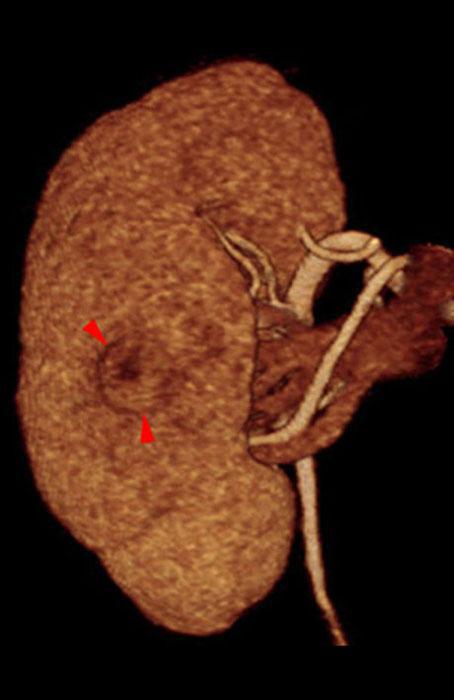

Recidiva local de hipernefroma